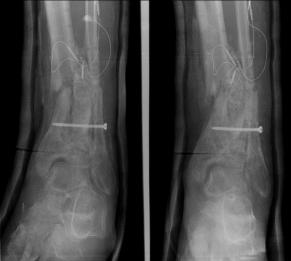

Post-corrective surgery X-Rays of the damaged right & left legs / ankles

The first two x-rays show Liam’s left ankle and pelvis prior to the accident. For comparison purposes it is interesting to see the

differences. The next x-rays were taken after the corrective surgery performed by Dr. Armendariz. Noticed that Dr. Armendariz has used tibia

bracing and also aligned the bone fragments of the left leg so that they could heal in the proper orientation. The external fixation has been

removed and Liam’s left foot has been returned to a more natural alignment.